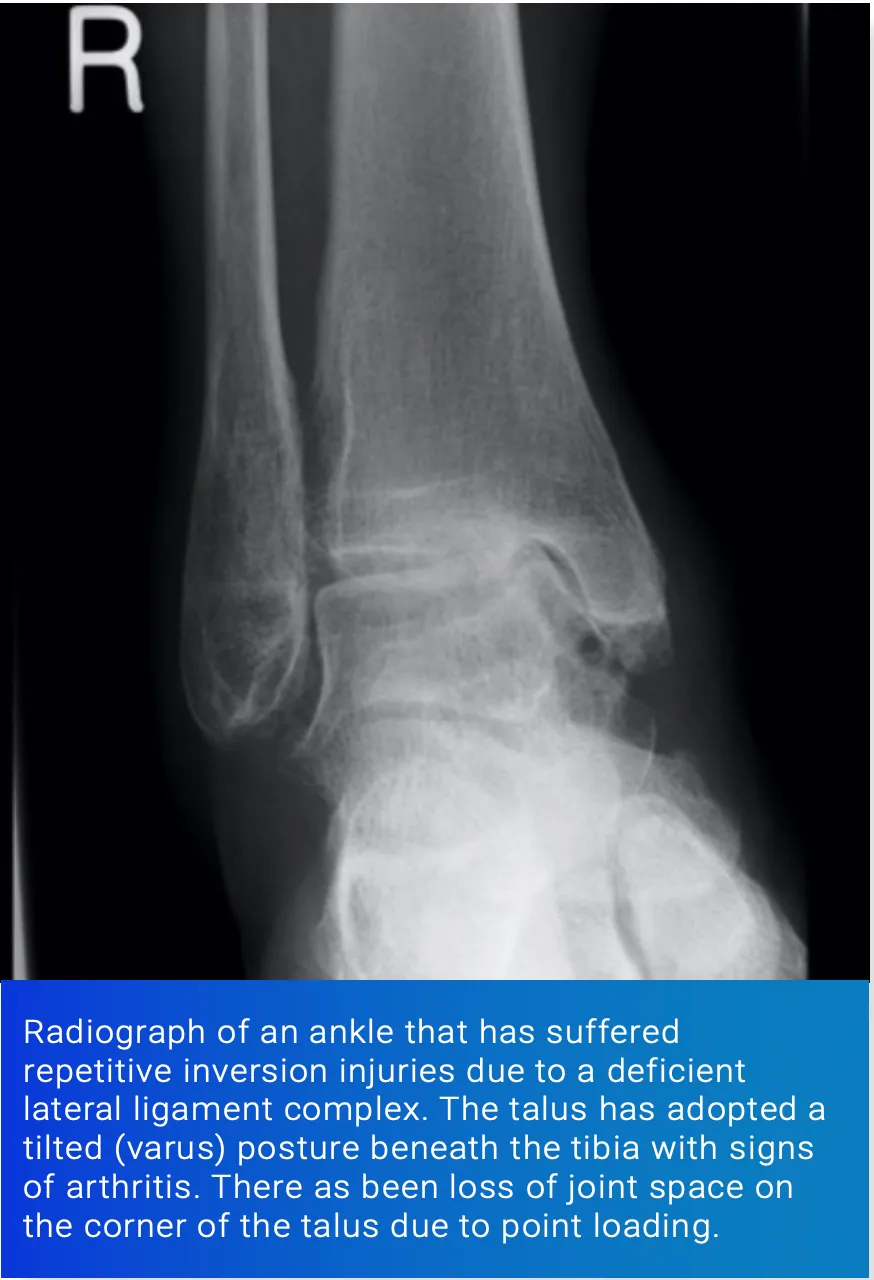

6) Chronic Instability of a Joint

Joint motion is stabilised and limited by ligaments. These ensure that the joint stays within its physiological range and avoids overload on the hyaline cartilage.

Injuries can cause rupture of the ligaments and result in joint instability. This can be a disabling problem in its own right requiring bracing, physiotherapy or reconstructive surgery.

Good examples include the lateral ligaments of the ankle and the anterior and posterior cruciate ligaments of the knee.

Chronic instability, such as can occur in patients that suffer significant ankle injury, can cause repetitive injury to the joint, resulting in eventual damage to the articular cartilage.